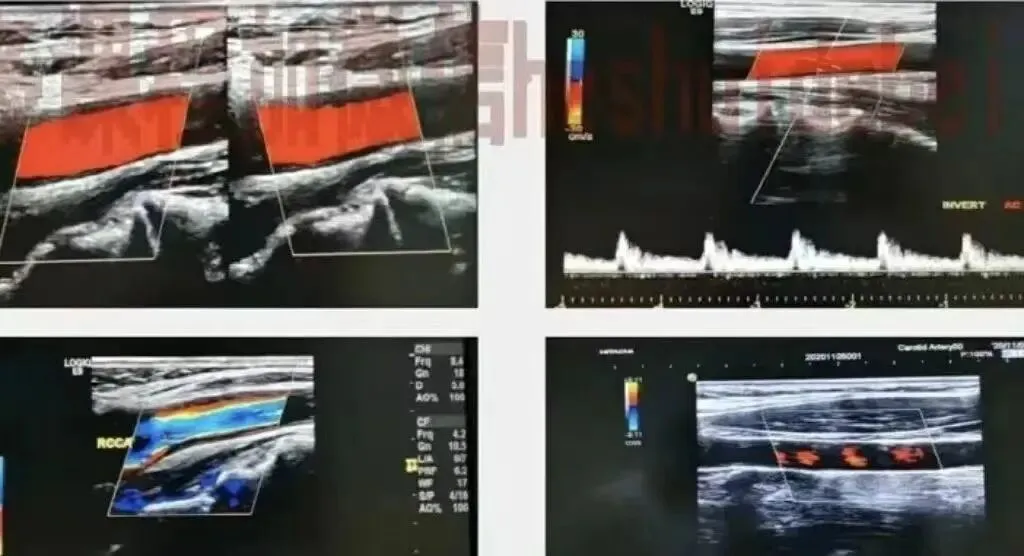

● 观察管腔内有无斑块、狭窄、闭塞等:测量斑块大小,注意斑块类型及形态等。

● 观察血管内血流充盈情况及观察狭窄或闭塞部位;测量血流参数。

颈动脉硬化斑块及狭窄率的界定

● 内-中膜检测:早期表现分为局限性或弥漫性颈动脉IMT融合,致IMT增厚,二维超声显示内-中膜融合,伴不均匀回声改变,IMT≥1.0mm界定为颈动脉内-中膜增厚,颈动脉分叉处IMT≥1.2mm为增厚。

● 动脉硬化斑块检测:当IMT≥1.5mm,凸出于血管腔内,或局限性内膜增厚高于周边IMT的50%,可定义为动脉硬化斑块形成。

颈部动脉狭窄的评估方法

● 直径测量法(B-A)/B*100%

残余管径

狭窄远段正常颈动脉管径

● 面积测量法:(A1-A2)/A1*100%

原始管径横截面积

残余管径横径面积

● 狭窄处血流速度法